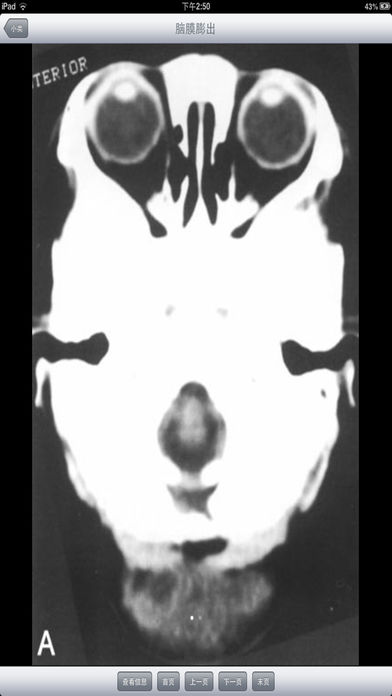

随着医疗卫生事业的发展,各种医疗仪器层出不穷的涌现,给临床诊断工作带来了极大的帮助,尤其是B超、CT、X光等影像学检查的应用,大大的提高了临床诊断的正确符合率和准确性。 基层诊断医生对影像知识缺乏了解,不能结合临床有重点的剖析,正确地加以辨别,诊断难以深刻,而且易忽略不典型病变,产生误诊、漏诊;另外,基层医生缺乏必要的影像读片知识,从而影像了诊断水平的提高。 影像诊断系统能够指导各级医生如何识别B超、CT、X光等临床表现,分析各种疾病的影像特征,做出更符合临床的影像诊断。每一张影像都配有表现和评述,是医生和医学院校的学生学习影像诊断入门的必备软件。